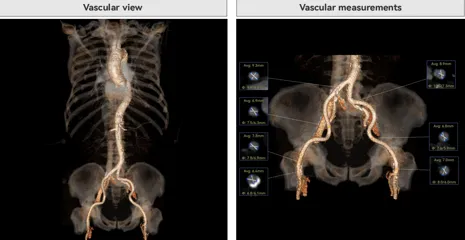

患者病史 男性,74y, 因 “发现心脏瓣膜病 1 年,加重伴喘气半年” 入院。门诊检查显示主动脉瓣重度AS并伴轻-中度AR。患者基础疾病较多:胸腹主动脉多发穿透性溃疡、心功能III级等,手术指征明确,但风险极高。 术前CT LVOT- Annulus 倒梯形,对植入瓣膜有挤压位移风险,Annulus直径23.7mm,瓣叶增厚,钙化集中在无冠窦边缘。 左冠脉开口高度可,瓣叶不长、窦部空间较大,无冠脉风险;室间隔膜部较短,有一定PPI风险,心脏角度37.9°;心室较小,有一定循环崩溃风险,术前注意补液。 术前造影角度及入路:血管入路散在钙化、无迂曲;主动脉弓条件好、双侧股动脉直径大、右股穿刺点侧壁存在环形钙化 左右重合位:RAO 7° CAU 21° 右窦中心位:LAO2 1° CAU 1° 手术策略 20mm球囊预扩后植入AV26瓣膜,同时做好预防循环崩溃、传导阻滞的应急预案。 术中挑战 1)球囊预扩:20mm球囊预扩时无明显 “腰征”,但存在少量反流,提示瓣膜钙化与解剖结构对扩张的阻力不均 2)首次释放偏差:第一次定位释放时,瓣膜在 “开花” 过程中下滑约 3mm,工作位观察显示小弯侧瓣周漏较多(深度超过完全覆膜区),需二次调整。 3)二次精准定位:以猪尾导管为参照,将定位点调整至 “猪尾 - 2mm” 处,结合真实窦底深度(较深)重新释放,最终瓣膜位置稳定,瓣周漏显著减少。 术后即刻效果: 瓣膜形态良好,跨瓣压差从术前的 67mmHg 降至 6mmHg,且无明显瓣周漏,冠脉开口通畅; Commisural Alignment 术后即刻超声: Prostyle A®预装干瓣——助力临床最优化解决方案: √ 平衡的径向支撑力:特殊的解剖结构下位置形态良好,术后跨瓣压差大幅降低,血流动力学改善明显; √ 80%可回收设计:支持术中二次调整释放位置,保证精准释放; √ 平衡的收腰设计&Commissural Alignment设计: 为患者后期冠脉PCI保留了生命通道;